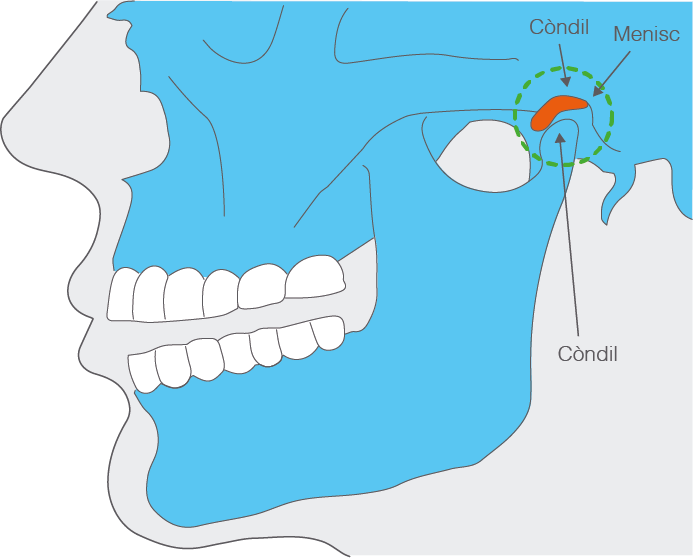

L’articulació temporomandibular és l’articulació de la mandíbula. N’hi ha dues, una al costat dret i l’altra al costat esquerre, que funcionen de manera sincrònica. El nom prové dels dos ossos que la formen: a la part superior, l’os temporal, i a la part inferior, el maxil·lar inferior o mandíbula (vegeu figura).

És l’única articulació mòbil del cap que permet executar els moviments masticatoris d’obertura i tancament de la boca, protrusió, retrusió i lateralitat. Es tracta d’una diartrosi bicondília. L’articulació es produeix entre el còndil temporal i el còndil de la mandíbula. Entre els còndils hi ha un coixinet de teixit fibrocartilaginós anomenat menisc. Entre els còndils i el menisc i ha unes cavitats anomenades cavitats sinovials i envoltant l’articulació hi ha una càpsula articular fibrosa.

A més, hi ha una relació d’interdependència entre l’articulació temporomandibular i la relació interdental de les dents dels dos maxil·lars, de manera que qualsevol trastorn patològic o funcional en alguna d’aquestes estructures pot alterar el funcionament dels elements constitutius. En ocasions se l’anomena articulació temporomandibulodental. Els odontòlegs l’anomenen de manera abreujada ATM.